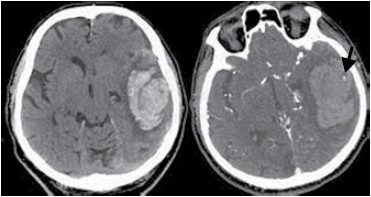

Homem, 60 anos, sem antecedentes prévios, foi admitido no pronto-socorro com quadro de afasia mista. Na admissão encontrava-se afebril, taquicárdico e pressão arterial de 210/103 mmHg. As imagens de tomografia de crânio realizadas estão a seguir. As setas indicam um sinal característico encontrado nas suspeitas de trombose venosa cerebral. Assinale a alternativa correta.

(Arquivo pessoal; imagem usada com autorização)